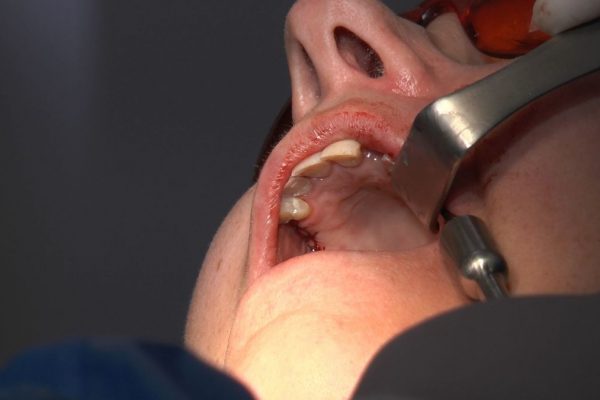

W ostatni weekend czerwca 2018 roku kursanci II Sezonu Preludium Implantologii odbyli piątą, finałową sesję, która w całości podporządkowana była praktyce. W ciągu dwóch dni zabiegowych Lekarze uczestniczący w szkoleniu przeprowadzili szereg zabiegów pod kierunkiem dr n.med. Violetty Szycik. Wszczepili 17 implantów oraz przeprowadzili ekstrakcje i zabiegi regeneracyjne kości. Zabiegi były wykonywane także w sedacji dożylnej z udziałem specjalisty anestezjologii i intensywnej terapii dr Jolanty Grzybowskiej. Preludium implantologii to nowy program edukacyjny dla adeptów implantologii stomatologicznej, którego celem jest wprowadzenie do implantologii poprzez pozyskanie wiedzy w szerokim zakresie i uwzględnieniem szczegółów mających decydujące znaczenie dla powodzenia leczenia implantologicznego. Ale tak jak wszystkie szkolenia w Instytucie Vivadental, w tym wiodące Practiculum Implantologii, zorientowane jest na praktyce i samodzielnym wykonywaniu zabiegów pod kierunkiem Mentora. To najlepsza edukacja w medycynie zabiegowej, a zarazem najlepszy start do implantologii.